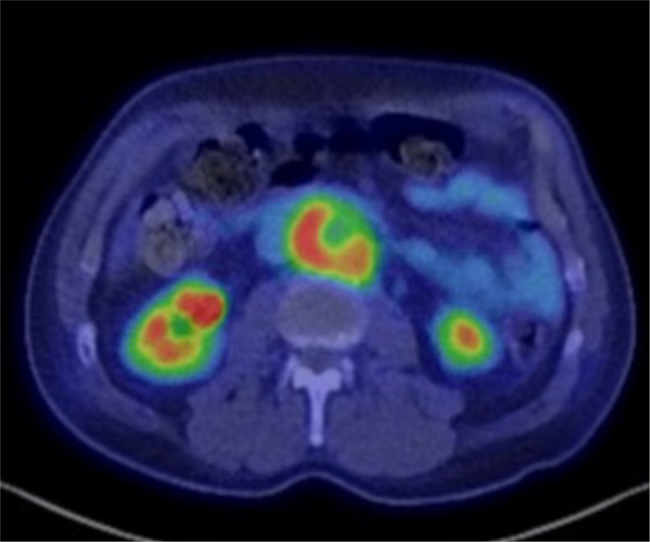

Case description: We report the case of a 70-year-old man presenting with flank pain and periaortitis, in whom positron emission tomography/computed tomography (PET/CT) scan revealed moderate-to-severe 18F-fluorodeoxyglucose (FDG) uptake. Despite negative cultures, a Karius test and urine antigen confirmed Streptococcus pneumoniae as the causative agent. The patient underwent successful open surgical repair of a mycotic pararenal abdominal aortic aneurysm, followed by targeted antibiotic therapy.

Discussion: Pneumococcal periaortitis is a rare condition with few reported cases, though S. pneumoniae has been implicated in various vascular infections including mycotic aneurysms, and diagnostic challenges persist, especially when blood cultures are negative. The Karius Spectrum, despite its cost and limited guidance for use, and FDG-PET/CT imaging have emerged as helpful tools in identifying infectious aetiologies, with high maximum standardized uptake value values favouring infection over autoimmune causes, as seen in this case.

Conclusion: Infectious periaortitis should be suspected when there is a high uptake of FDG on PET/CT prompting an infectious disease work-up which may include a Karius test.